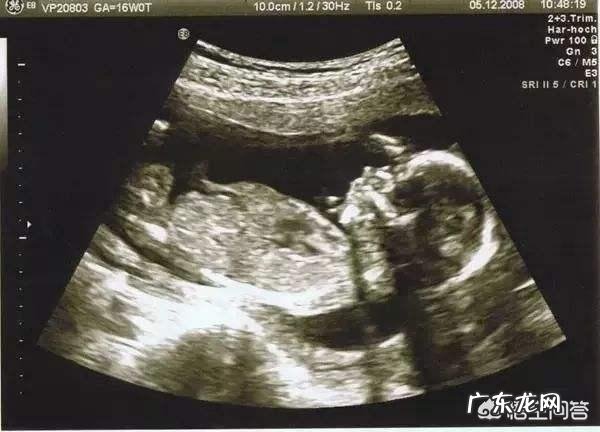

怀孕4个月也就是16周,此时宝宝还没有进入快速生长期,宝妈们对宝宝的生长发育不要过于严格 。只要注意营养,定时监测胎儿生长发育情况就行 。下图是B超下孕4个月的胎儿大小 。

正常情况下,孕4月的胎儿双顶径的平均值为3.62±0.58cm,股骨长的平均值为2.10±0.51cm 。题主给出的数据为双顶径4.1cm,股骨长2.5cm 。对比上述数据应该是正常范围内的,属于偏大一点 。